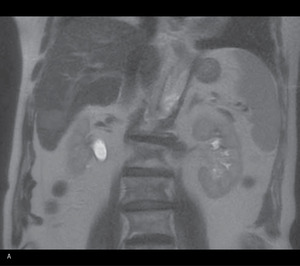

Badaniem mającym zadecydować o możliwości takiego leczenia był rezonans magnetyczny (MR) wykonany po czterech miesiącach od ustalenia rozpoznania (ryc. 1).

Rycina 1. Obraz MR przed leczeniem. (A) W projekcji osiowej widoczna zmiana w segmencie 6. (B) Na przekroju poprzecznym w segmencie 4 widoczna zmiana w okolicy pęcherzyka żółciowego

Stwierdzono powiększenie rozmiarów opisywanych wcześniej ognisk w wątrobie. Zmiana położona w segmencie 4a, w okolicy pęcherzyka żółciowego, osiągnęła wymiary 7,3 × 6 cm, a zmiana w segmencie 6 – 3 × 2 cm. W segmentach 5 i 7 uwidoczniono też nowe ogniska o średnicy poniżej 1 cm, nieulegające wzmocnieniu po podaniu środka cieniującego, dostrzegalne jedynie na obrazach T2-zależnych oraz w badaniu wykonanym metodą obrazowania dyfuzyjnego (DWI – diffusion-weighted imaging). Pozostały miąższ wątroby wykazywał cechy przebudowy marskiej. Nie uwidoczniono innych nieprawidłowości w obrębie jamy brzusznej, w tym powiększonych węzłów więzadła wątrobowo-dwunastniczego.